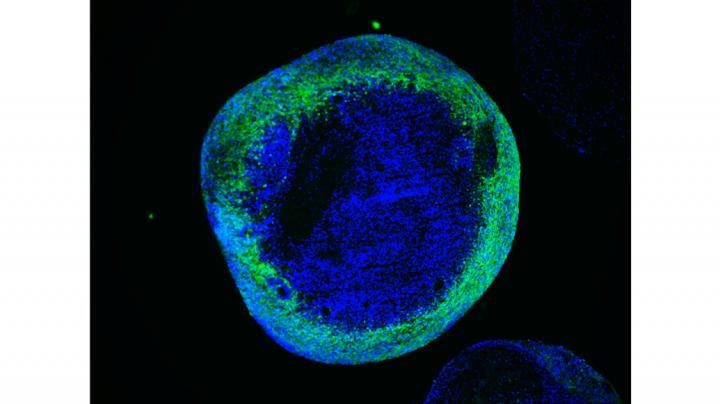

image: In brain organoids from Leigh syndrome patients, neurons do not mature properly. This is due to an impaired activation of mitochondrial metabolism in cells that generate neurons which are called neural precursors. The authors demonstrate that helping the activation of mitochondrial metabolism in neural precursors can revert the defects. They achieved this using two strategies that may be applicable in the clinics: 1) gene correction with CRISPR/Cas9 or viral-based delivery of the healthy gene, 2) increasing the expression of the metabolic regulator PGC1-alpha using the FDA-approved drug Bezafibrate.

Copyright: Dr. Agnieszka Rybak-Wolf

To achieve this, the authors employed the technology of cellular reprogramming, which enables to convert cells from the skin into stem cells that are capable of generating neurons. They then used the molecular scissors CRISPR/Cas9 to precisely remove the mutation from the patient cells and to introduce the mutations into the control cells. Thus the authors were able to investigate the specific effect of SURF1 mutations in a controlled genetic background. They next generated neurons and brain organoids, which are of a three-dimensional structure and reproduce the features of early human brain development.

Using these models, the authors discovered that the neuronal defects seen in the patients may be caused by an energy deficit occurring at the level of neural precursors, which are the cells that generate neurons. These energy defects lead to insufficient neuronal branching, which causes improper brain function during development. Finally, the authors demonstrate that the neuronal branching defects can be corrected by improving the energy output of progenitor cells using SURF1 gene replacement therapy or by using the drug Bezafibrate, which is currently safe for clinical use in children.